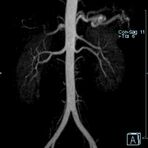

Aorta

• Bauchgefäße

• Erfassung und Verlaufskontrolle bei arteriellen Aneurysmen (Aussackungen der Arterien), vor allem der Bauchaorta

• Darstellung von Gefäßengen an Nierenarterien, Baucharterien und Becken-/Beinarterien

Ganzkörper Angiographie mit Kontrastmittel

• MR-Angiographie mit Kontrastmittel

• Erfassung arterieller und venöser Gefäße/Bypässe aller Körperregionen mit 3D-Rekonstruktion

• je nach klinischer Fragestellung zeitaufgelöste MR-Angiographie (4D-MRA) z.B. bei Frage arteriovenöse Fistel/ Shunt oder Darstellung Unterschenkelarterien vor geplanter Bypassoperation.